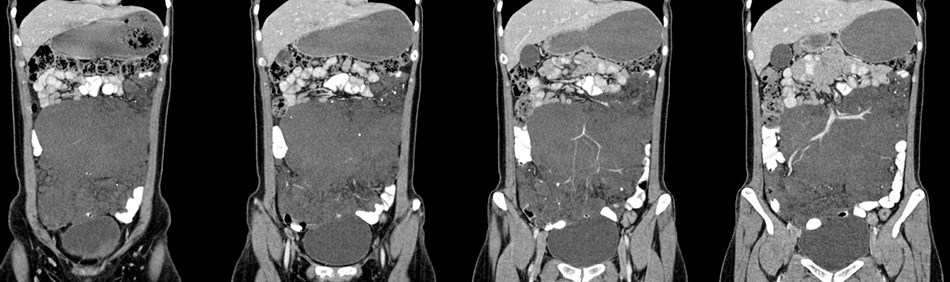

女性,28岁,停经3月,腹部膨隆1月,产前检查发现腹部占位

{肿块中心ct值27hu,增强后,动脉期、门脉期均无明显强化)

1 肠系膜肿块诸期无明显强化,肠系膜血管包绕其中但其周围仍见脂肪称“脂肪环征”;2 肠系膜血管远端较近端细,于重组像上见血管周围有强化结节为炎性结节,3肿块内见部分脂肪密度及少许点状钙化。4 腹膜后无肿大ln。

患者手术病理:腹腔囊性淋巴管瘤,象这样充满整个腹腔的的确很少见